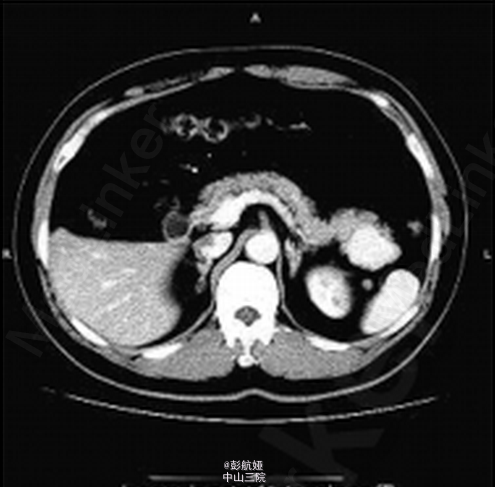

患者 ,男 ,56岁 ,因“体检发现胰尾部占位 2周”入院 ,入院后无明显阳性体征 。 实验室检查 :肿瘤标志物甲胎蛋白6.57ng/mL ,癌胚抗原 3.64ng/mL ,糖类抗原1259.90U/mL ,糖 链抗原 19-912.30 U/mL ,鳞状细胞癌相关抗原0.8ng/mL 。B超检查 :胰腺切面形态失常 ,胰尾部可见一大小3.5 cm × 2.8cm 低回声区 ,边界尚清 ,内部回声不均。胰管不扩张。 彩色多 普勒(CDFI) :门静脉血流充盈 ,上述胰尾部低回声区内未见明显血流信号 ,余部位未见异常血流信号 。 B 超诊断 :胰尾部实质性病灶 。 CT 增强检查 :胰腺尾部可见一肿块影 ,大小约 4.4cm × 3.4 cm × 2.4 cm ,动脉期 、静脉期明显强化(图1、2) ,延迟期强化程度减低 ,且均匀强化(图 3) ,胰尾向前推移 ,肿块位于脾动静脉前下方 ,胰管未见扩张 。脾脏不大 ,密度均匀。 CT 诊断 :胰尾后方肿块、强化 ,多考虑肿瘤性病变 。手术及病理 :行全腹腔镜下胰体尾切除术 。切开胃结肠韧带 ,显露胰腺 ,可见胰腺体尾部约 5 cm × 3 cm 肿块 ,凸向胰体尾背侧生长 ,脾血管未受侵犯。 行胰体尾切除。病理 :送检组织镜下见为基本正常的胰腺组织 ,部分包裹脾脏组织 ,脾小体结构清楚 。符合(胰体尾)副脾 。